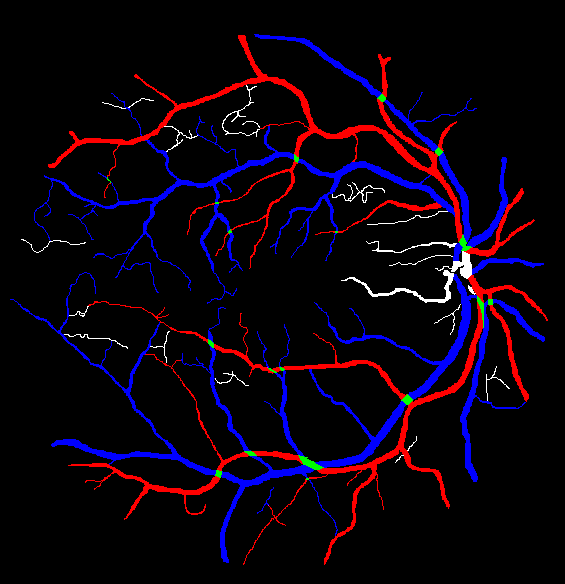

The visual differentiation between arteries and veins can be difficult in some cases, like small vessels with poor contrast and not clearly connected to a specific arterial or venular tree. These cases can be identified with certainty as vessels, but their classification into arteries and veins is uncertain, even for an expert. Additionally, it is common to find crossings between arteries and veins in the retina. Thus, although for these positions either the artery or the vein is above the other, these pixels can be regarded as simultaneously belonging to both types of vessels. This allows to account for continuous arterial and venular trees regardless of crossings below the other one. The identification of these two special situations (uncertain vessels, and vessel crossings) is common in manually annotated retinal vessel classification datasets [38, 42, 43, 44]. Figure 1 shows an example of a ground truth image from the RITE dataset labelled this way, along with its decomposition into arteries, veins, crossings and uncertain vessels.

Also, an example of a retinography and its corresponding vasculature segmentation and A/V classification ground truths is depicted in Figure 6.

In order to train the networks following the traditional and MS approaches, the ground truth images from the RITE dataset are adapted, in each case, to the output of the network. In the traditional approach, each pixel of the ground truth is assigned to either background, artery, vein or “uncertain or crossing” class, which comprises both uncertain vessels and crossings. The resulting ground truth is a grayscale image in which each pixel has a numeric label of the class to which it belongs. On the other hand, in the MS approach, each pixel is assigned to any number of the following classes: artery, vein and vessel. In this case, crossings belong to the three classes, and uncertain vessels belong only to the “vessel” class. Background pixels are not assigned to any class. The resulting ground truth is an RGB image in which each channel contains a manual segmentation mask of one of the aforementioned structures. An example of a RITE ground truth adapted to both the traditional and the MS approaches can be found in Figure 7.